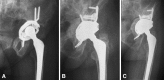

Methods: We prospectively followed 33 selected patients who underwent isolated acetabular revisions with a minimum of 2 years' followup (mean, 3 years; range, 2-5 years). In 24 patients a stainless steel dual-mobility cup was cemented into an antiprotrusio cage, whereas in nine we used a hyaluronan dual-mobility revision cup with a foramen hook and superior and posterior flanges screw fixations. We determined Harris hip (HHS) and WOMAC scores and examined radiographs for migration, loosening, and osteolysis.

Results: There were no dislocations. Survivorship rates of the femoral and acetabular components were 97% at 5 years; the rerevision rate for any reason was 3%. At last followup, the mean HHS increased from 48 points preoperatively to 86 points. No patients had progressive osteolysis, component migration, or loosening on radiographs.

Conclusion: In this select group of isolated acetabular revisions, our data suggest the use of a dual-mobility cup reduced the risk of dislocation without increasing loosening from 2 to 5 years.